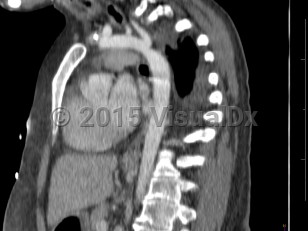

Coarctation of the aorta

Narrowing of the descending aorta distal to the take-off of the great vessels. Posterior costal arteries and internal mammary and scapular arteries provide collateral flow to the descending aorta. Usually congenital, although can be acquired as a consequence of inflammatory diseases affecting the aorta (eg, Takayasu arteritis). Clinical manifestations vary by age and associated cardiac defects, which may include bicuspid aortic valve, atrial septal defect (ASD), ventricular septal defect (VSD), patent ductus arteriosus, and D-transposition of the great vessels.